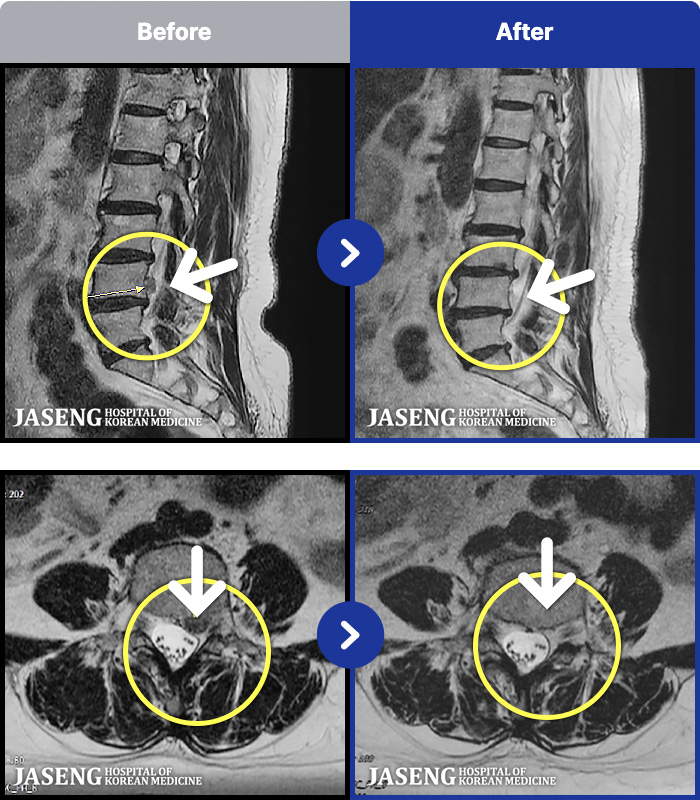

MRI ġ

1,240 MRI ũ ʸ Ȯϼ.